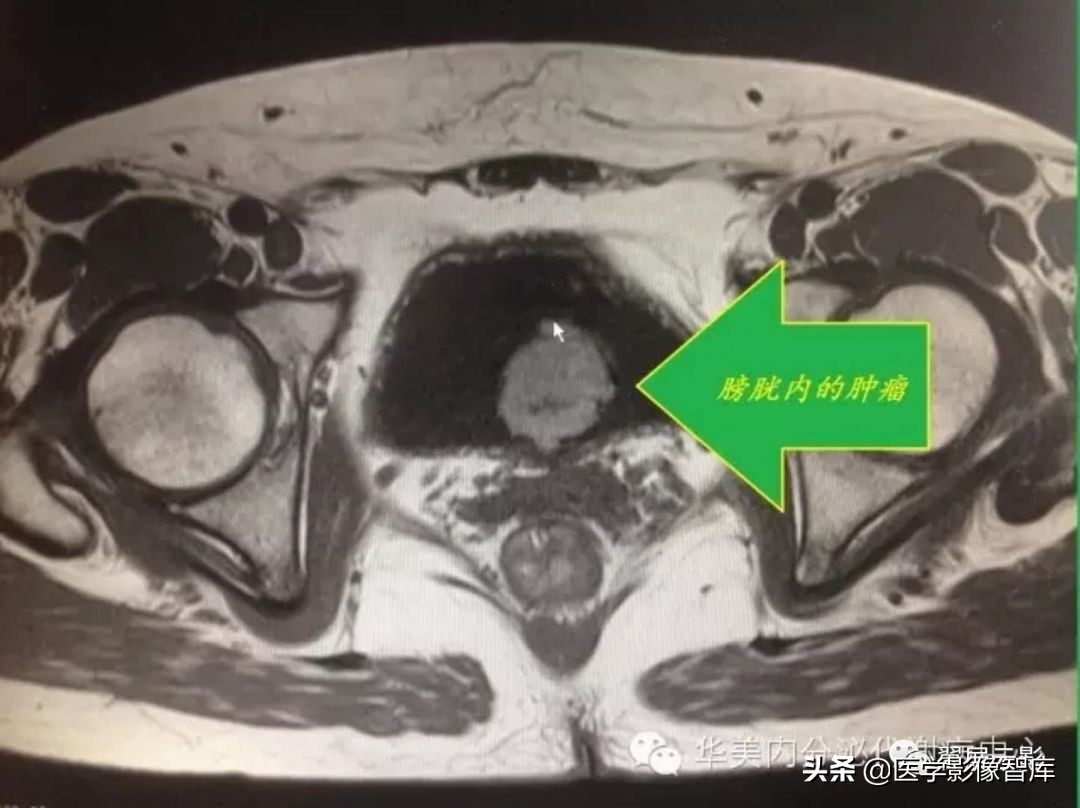

膀胱癌

膀胱肿瘤中膀胱癌最常见,常见于40岁以上男性,临床表现为血尿,可伴有尿痛和尿急,病理上主要为移行细胞癌,多呈乳头状向腔内生长,还可向外侵犯肌层,进而侵犯周围组织和器官,部分膀胱癌呈浸润性生长,造成膀胱壁局限性增厚。

本病的MRI表现主要为突入膀胱内的肿块和膀胱壁的局限性增厚,平扫T1WI呈低信号时可能显示不清,T2WI小肿瘤可能被尿液高信号掩盖,所以增强扫描必不可少,MRI可以对肿瘤进行分期,判断膀胱肌壁受侵程度,此时注意描述正常膀胱壁T2WI低信号带连续性中断,膀胱周围脂肪受侵时T1WI或T2WI脂肪信号区内有低信号影。